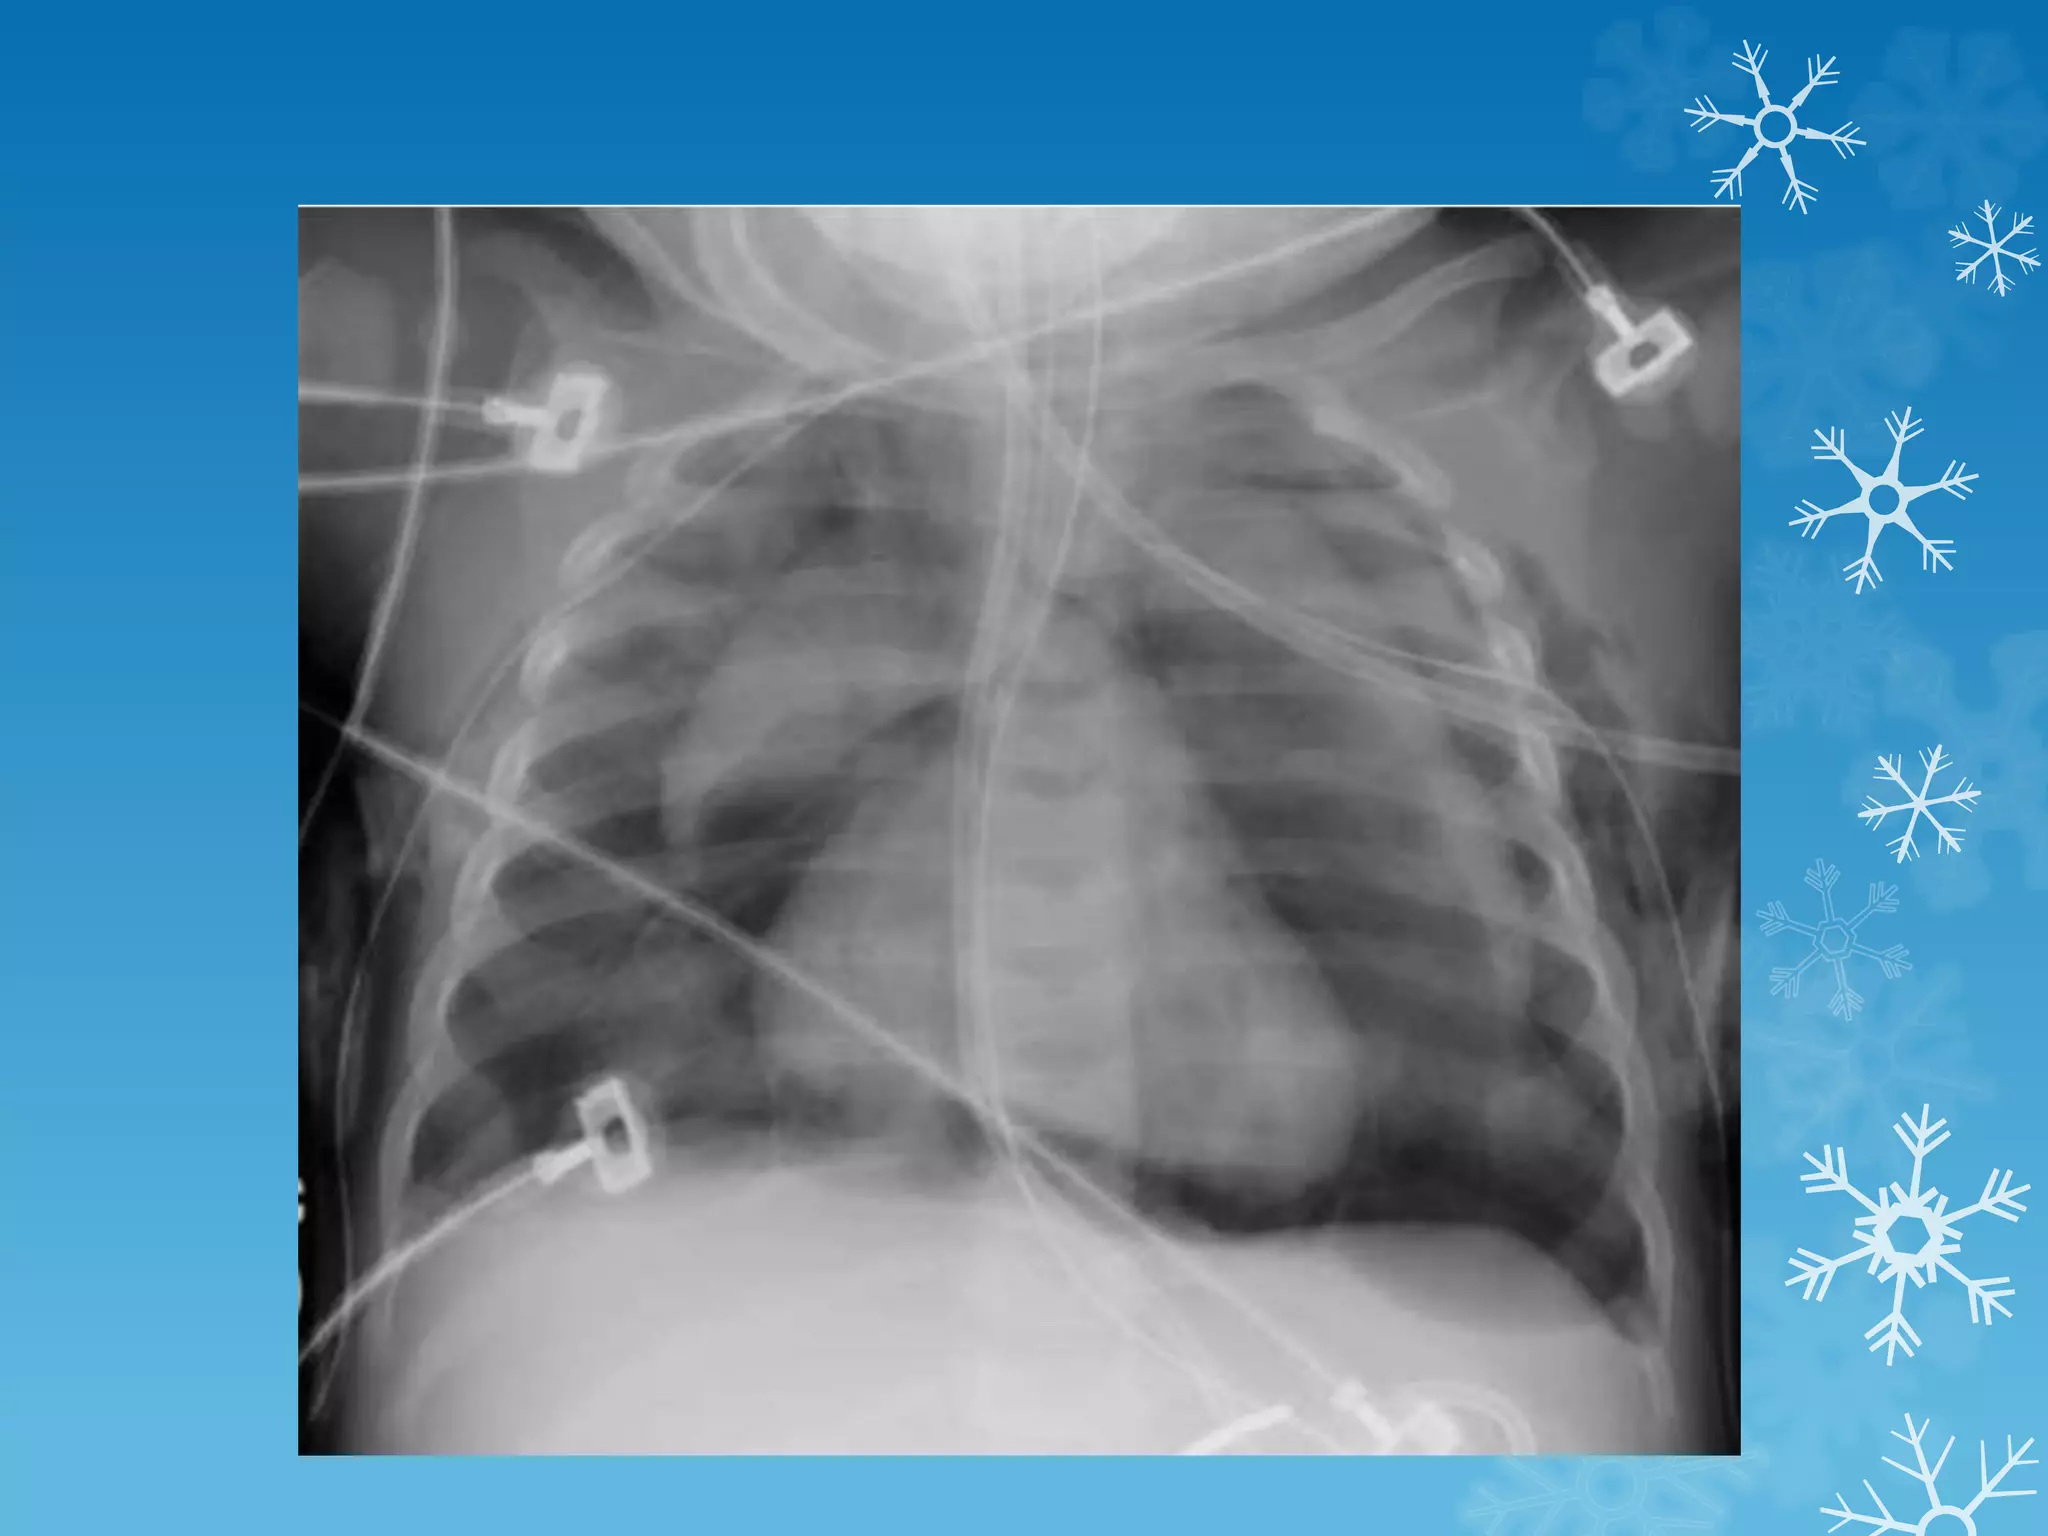

K/C/O AML on treatment

HRCT chest reveals bilateral diffuse GGO with air space consolidation and

subpleural sparing and a few air cysts classical of Pneumocystis jiroveci

pneumonia

Pneumocystis jiroveci pneumonia (PCP)